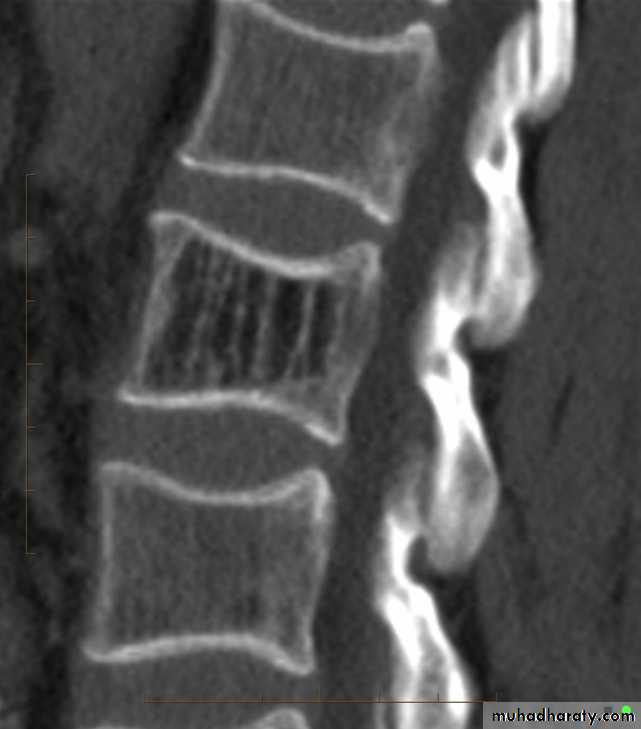

Ankylosing spondylitis-early

(A) Serrated marginsof sacroiliac joints and peri articular sclerosis.

(B) CT scanning demonstrates bilateral sacroiliitis